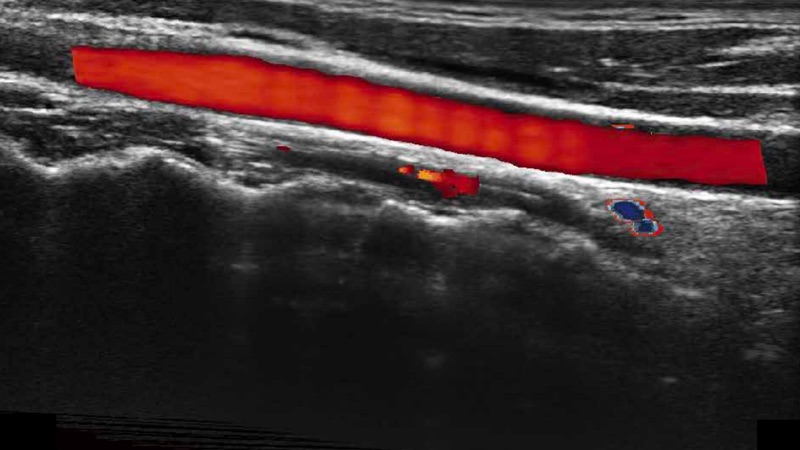

凸陣、線陣和相控陣探頭進(jìn)行實時掃描時,開啟擴(kuò)展成像模式,可以擴(kuò)展超聲圖像視野,以便更完整地查看大的病灶或組織器官的解剖結(jié)構(gòu)。

通過色彩血流和實時寬景相結(jié)合,可觀察到完整的靜脈或動脈的血流,方便醫(yī)生檢查。實時掃查過程中,如有任何操作失誤也可以很容易地進(jìn)行回掃擦除,而不會中斷掃查。